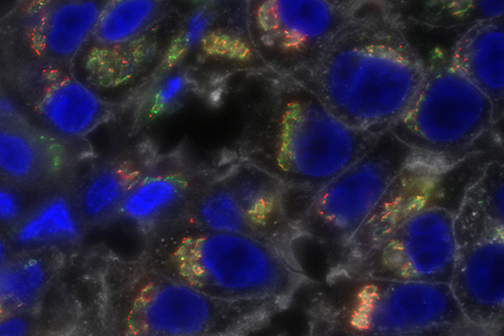

LSU Health New Orleans Develops New Human Cell Line to Study Blinding Eye Disorders

Under the direction of Boyd Professor Nicolas Bazan, MD, PhD, scientists at LSU Health New Orleans Neuroscience Center of Excellence have developed a new, experimental human cell line from retinal pigment epithelial cells. Called ABC, these cells so closely resemble and retain the properties of native retinal pigment epithelial (RPE) cells, the research team has shown that they are a reliable cell system to study retinal degenerative diseases. More